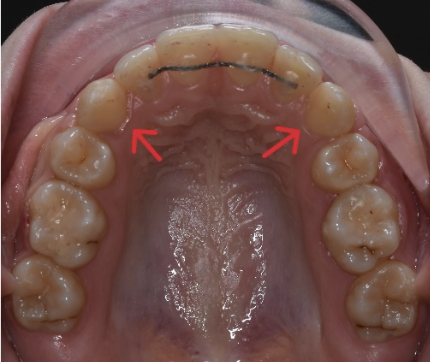

Iar acesta este aspectul final: